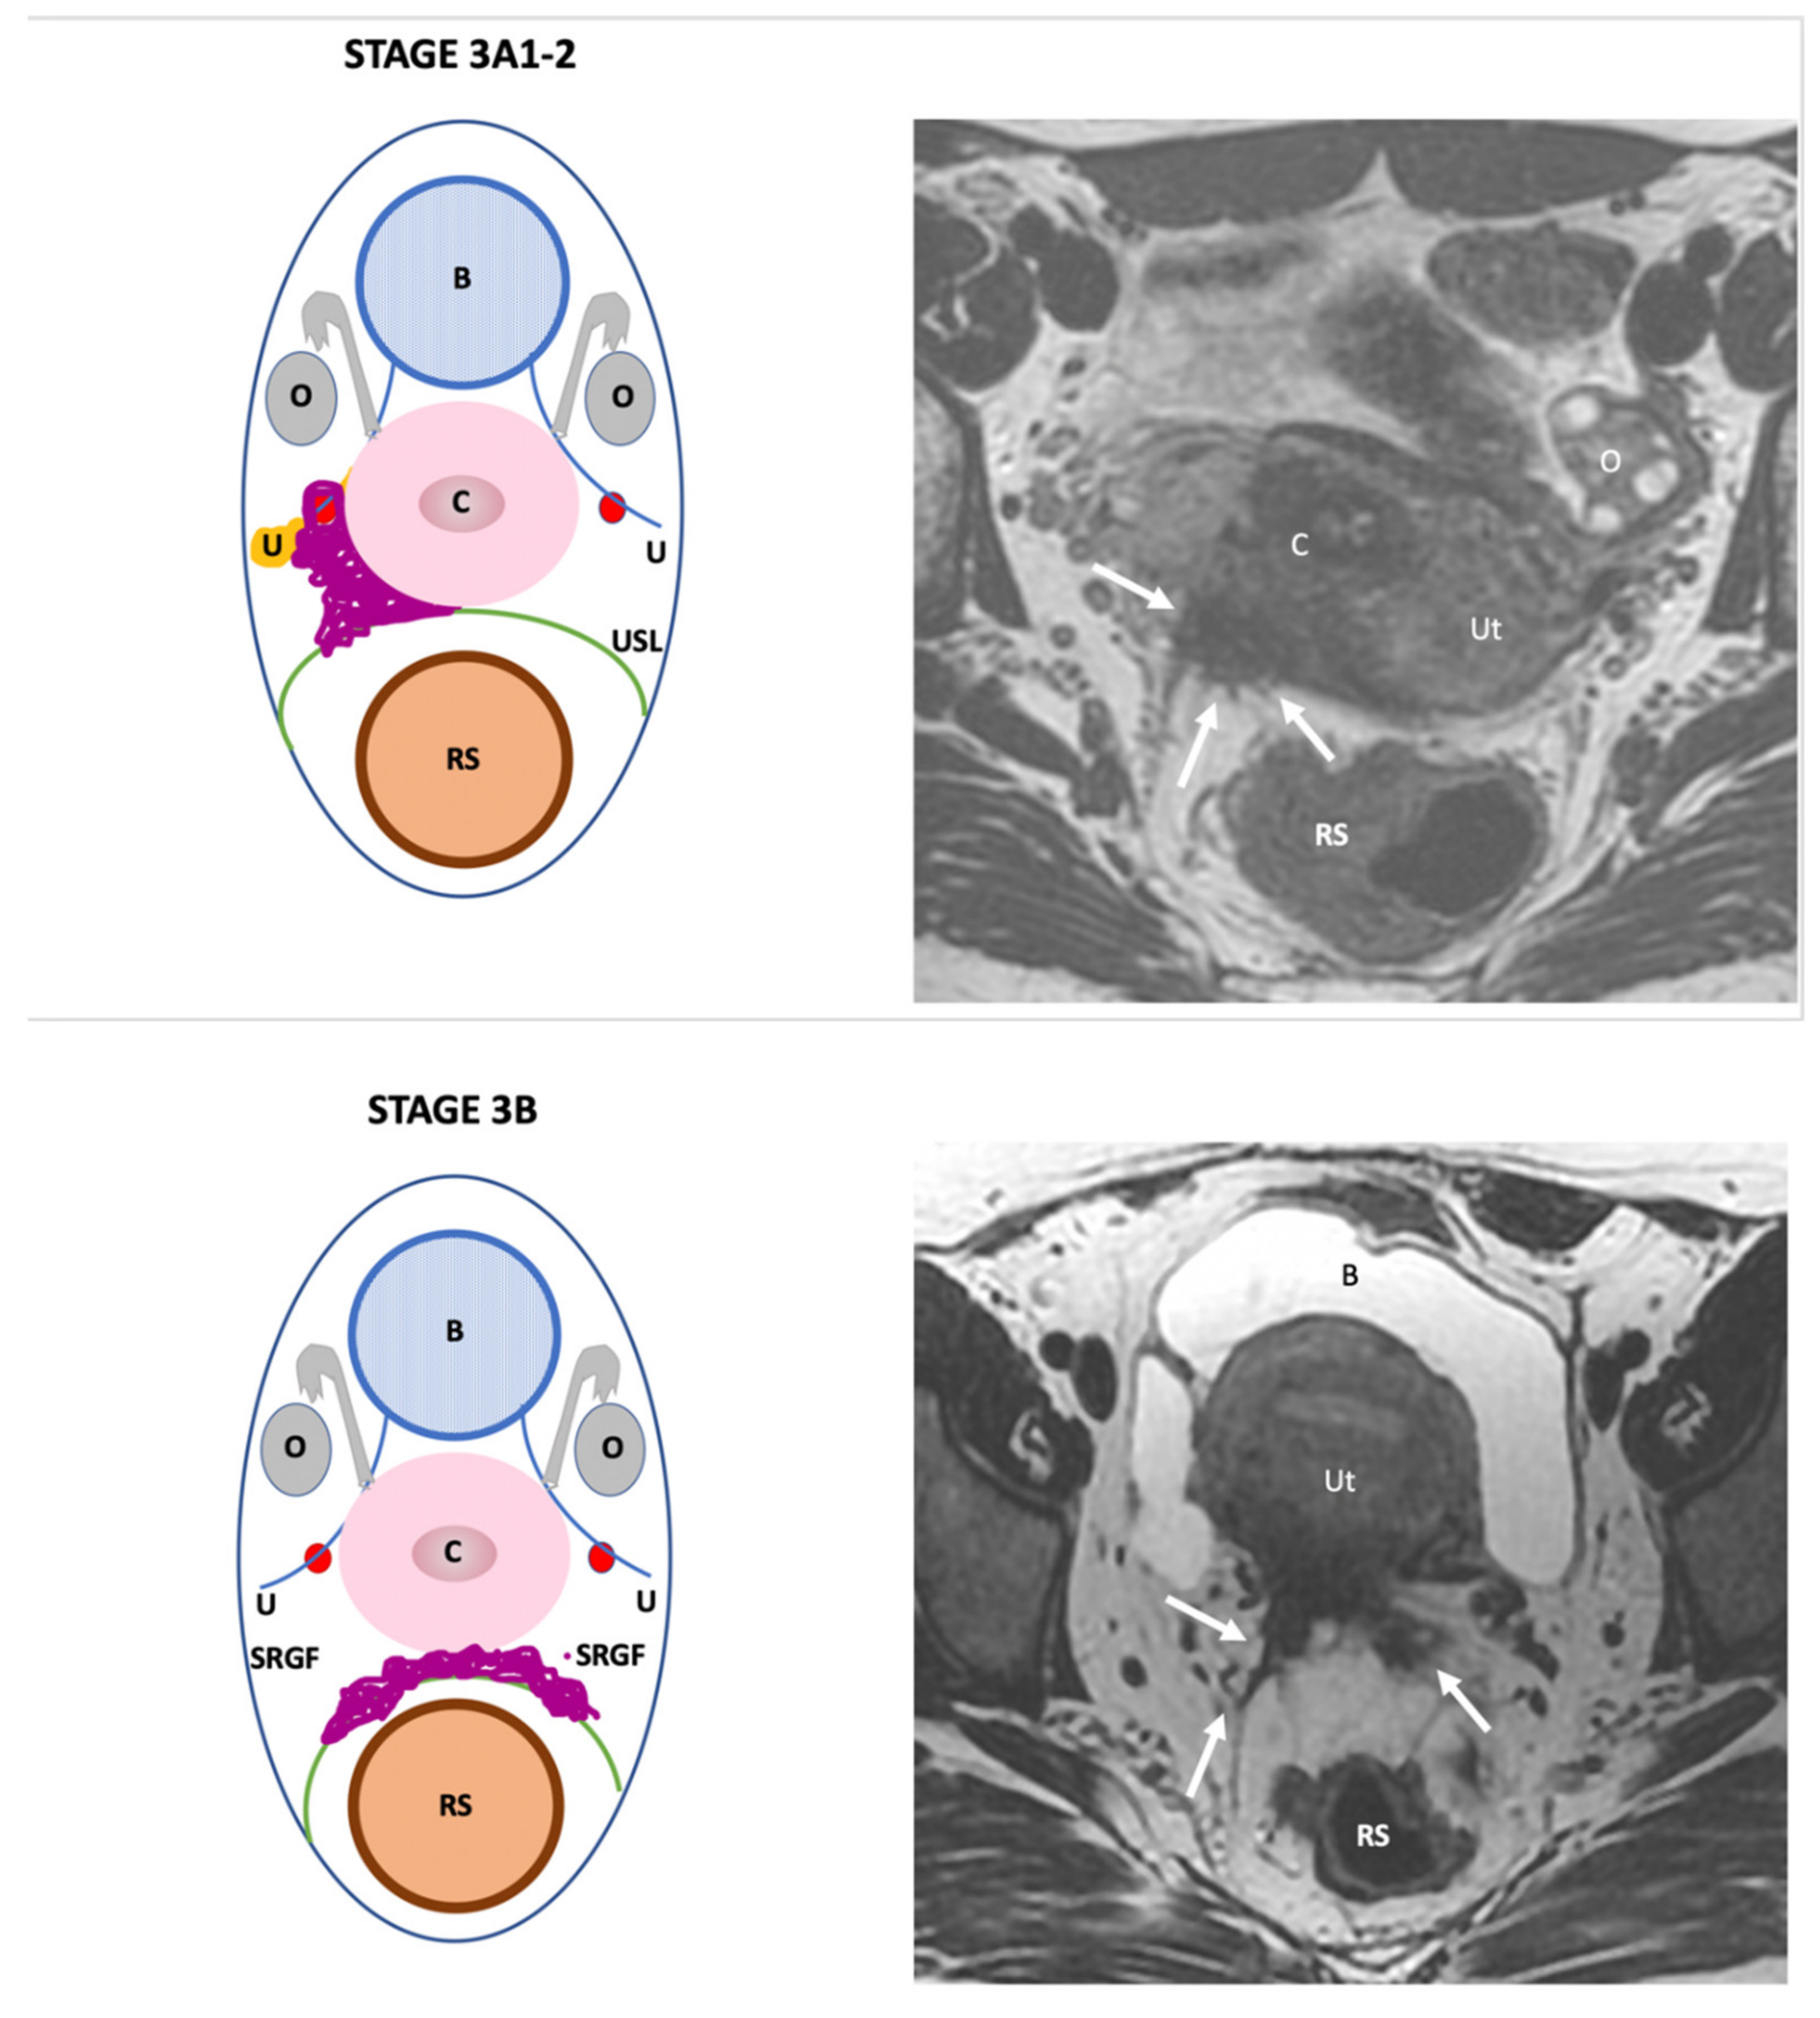

| Endo-Stage MRI III | Endometriosis extends to the pelvic side-wall and/or causes hydronephrosis or non-functioning kidney |

| Intermediate |